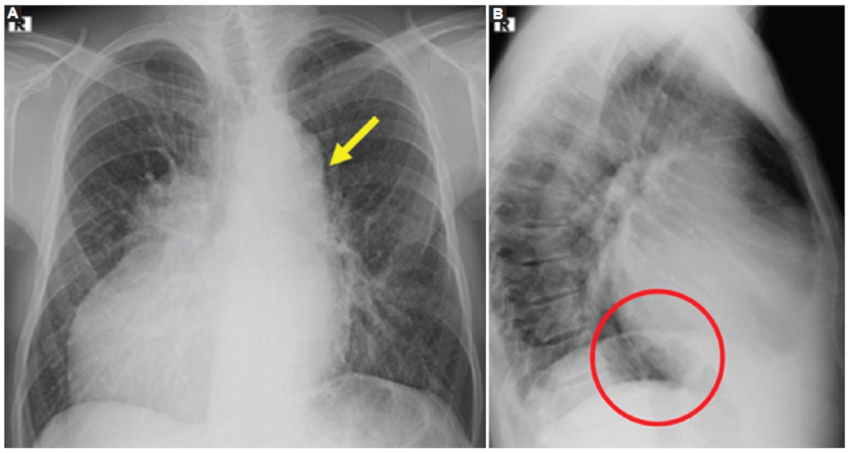

En el caso 2 se observó dextrocardia con ambas aurículas de morfología izquierda y comunicación interauricular tipo seno venoso adyacente a la inserción de la vena cava superior. En un tiempo precoz luego de la administración de medio de contraste se demostró opacificación de la aurícula contralateral, lo que sugiere shunt derecha-izquierda (Fig. 2 A y B). En el caso 3 se evidenció corazón unicameral con canal auriculoventricular (Fig. 2C).

Pulmones y bronquios

El síndrome de heterotaxia con isomerismo izquierdo se asocia a pulmones simétricos, bilobulados con una única cisura, como se observó en los casos 1, 2 y 3 (Figs. 3 y 4).

Los bronquios fuente son largos bilateralmente y pasan por debajo de la arteria pulmonar correspondiente, comportándose ambos como bronquios fuente izquierdos. Presentan bifurcación anatómica izquierda (bronquio lobar superior e inferior) y la distancia entre la carina y la primera división del bronquio princial es igual en ambos pulmones.